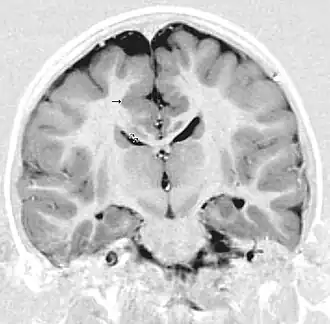

La polymicrogyrie est principalement une anomalie de l'organisation corticale des neurones probablement par un trouble de la migration des neurones à l'origine des dernières couches cellulaires du cortex cérébral : le cortex cérébral est plus épais avec de multiples circonvolutions.

Le diagnostic repose uniquement sur l'imagerie à résonance magnétique. La polymicrogyrie peut être isolée ou associée à d'autres anomalies : agénésie du corps calleux, schizencéphalie. Les diagnostics différentiels principaux sont la pachygyrie et la lissencéphalie.